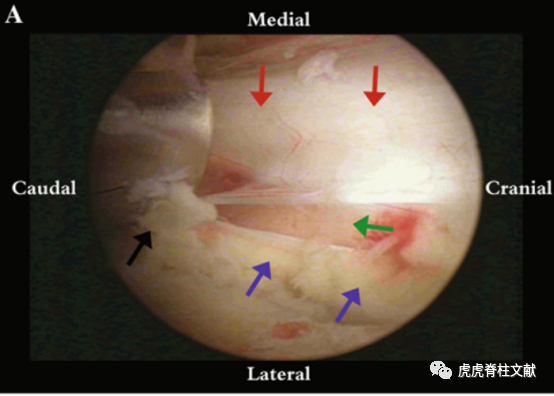

3.A.硬膜表面减压后的内镜图像;B.同侧走行神经根;C.对侧走行神经根